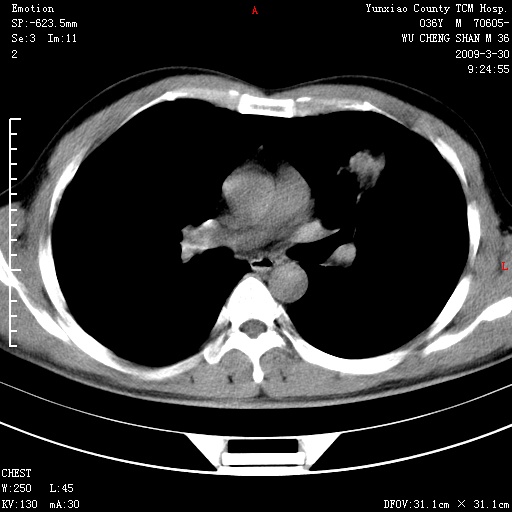

本院家属,胸痛,无咳嗽咳痰发烧病史,治疗一个月后病灶无明显改变,支气管镜示左肺慢性炎症,未见癌细胞,

临床资料不全,就影像资料来看,诊断炎性病变应该不错,肺结核?如果硬要考虑肺泡癌 证据不足!

建议:1)上传全部资料 观察纵隔内情况 2)完善实验室检查。

胸痛,无咳嗽咳痰发烧病史,治疗一个月后病灶无明显改变,支气管镜示左肺慢性炎症,未见癌细胞,左肺下叶前段片状影,边缘不清,内见空支气管征,纵隔未见淋巴结肿大,周围无卫星灶,应考虑为炎性病变。